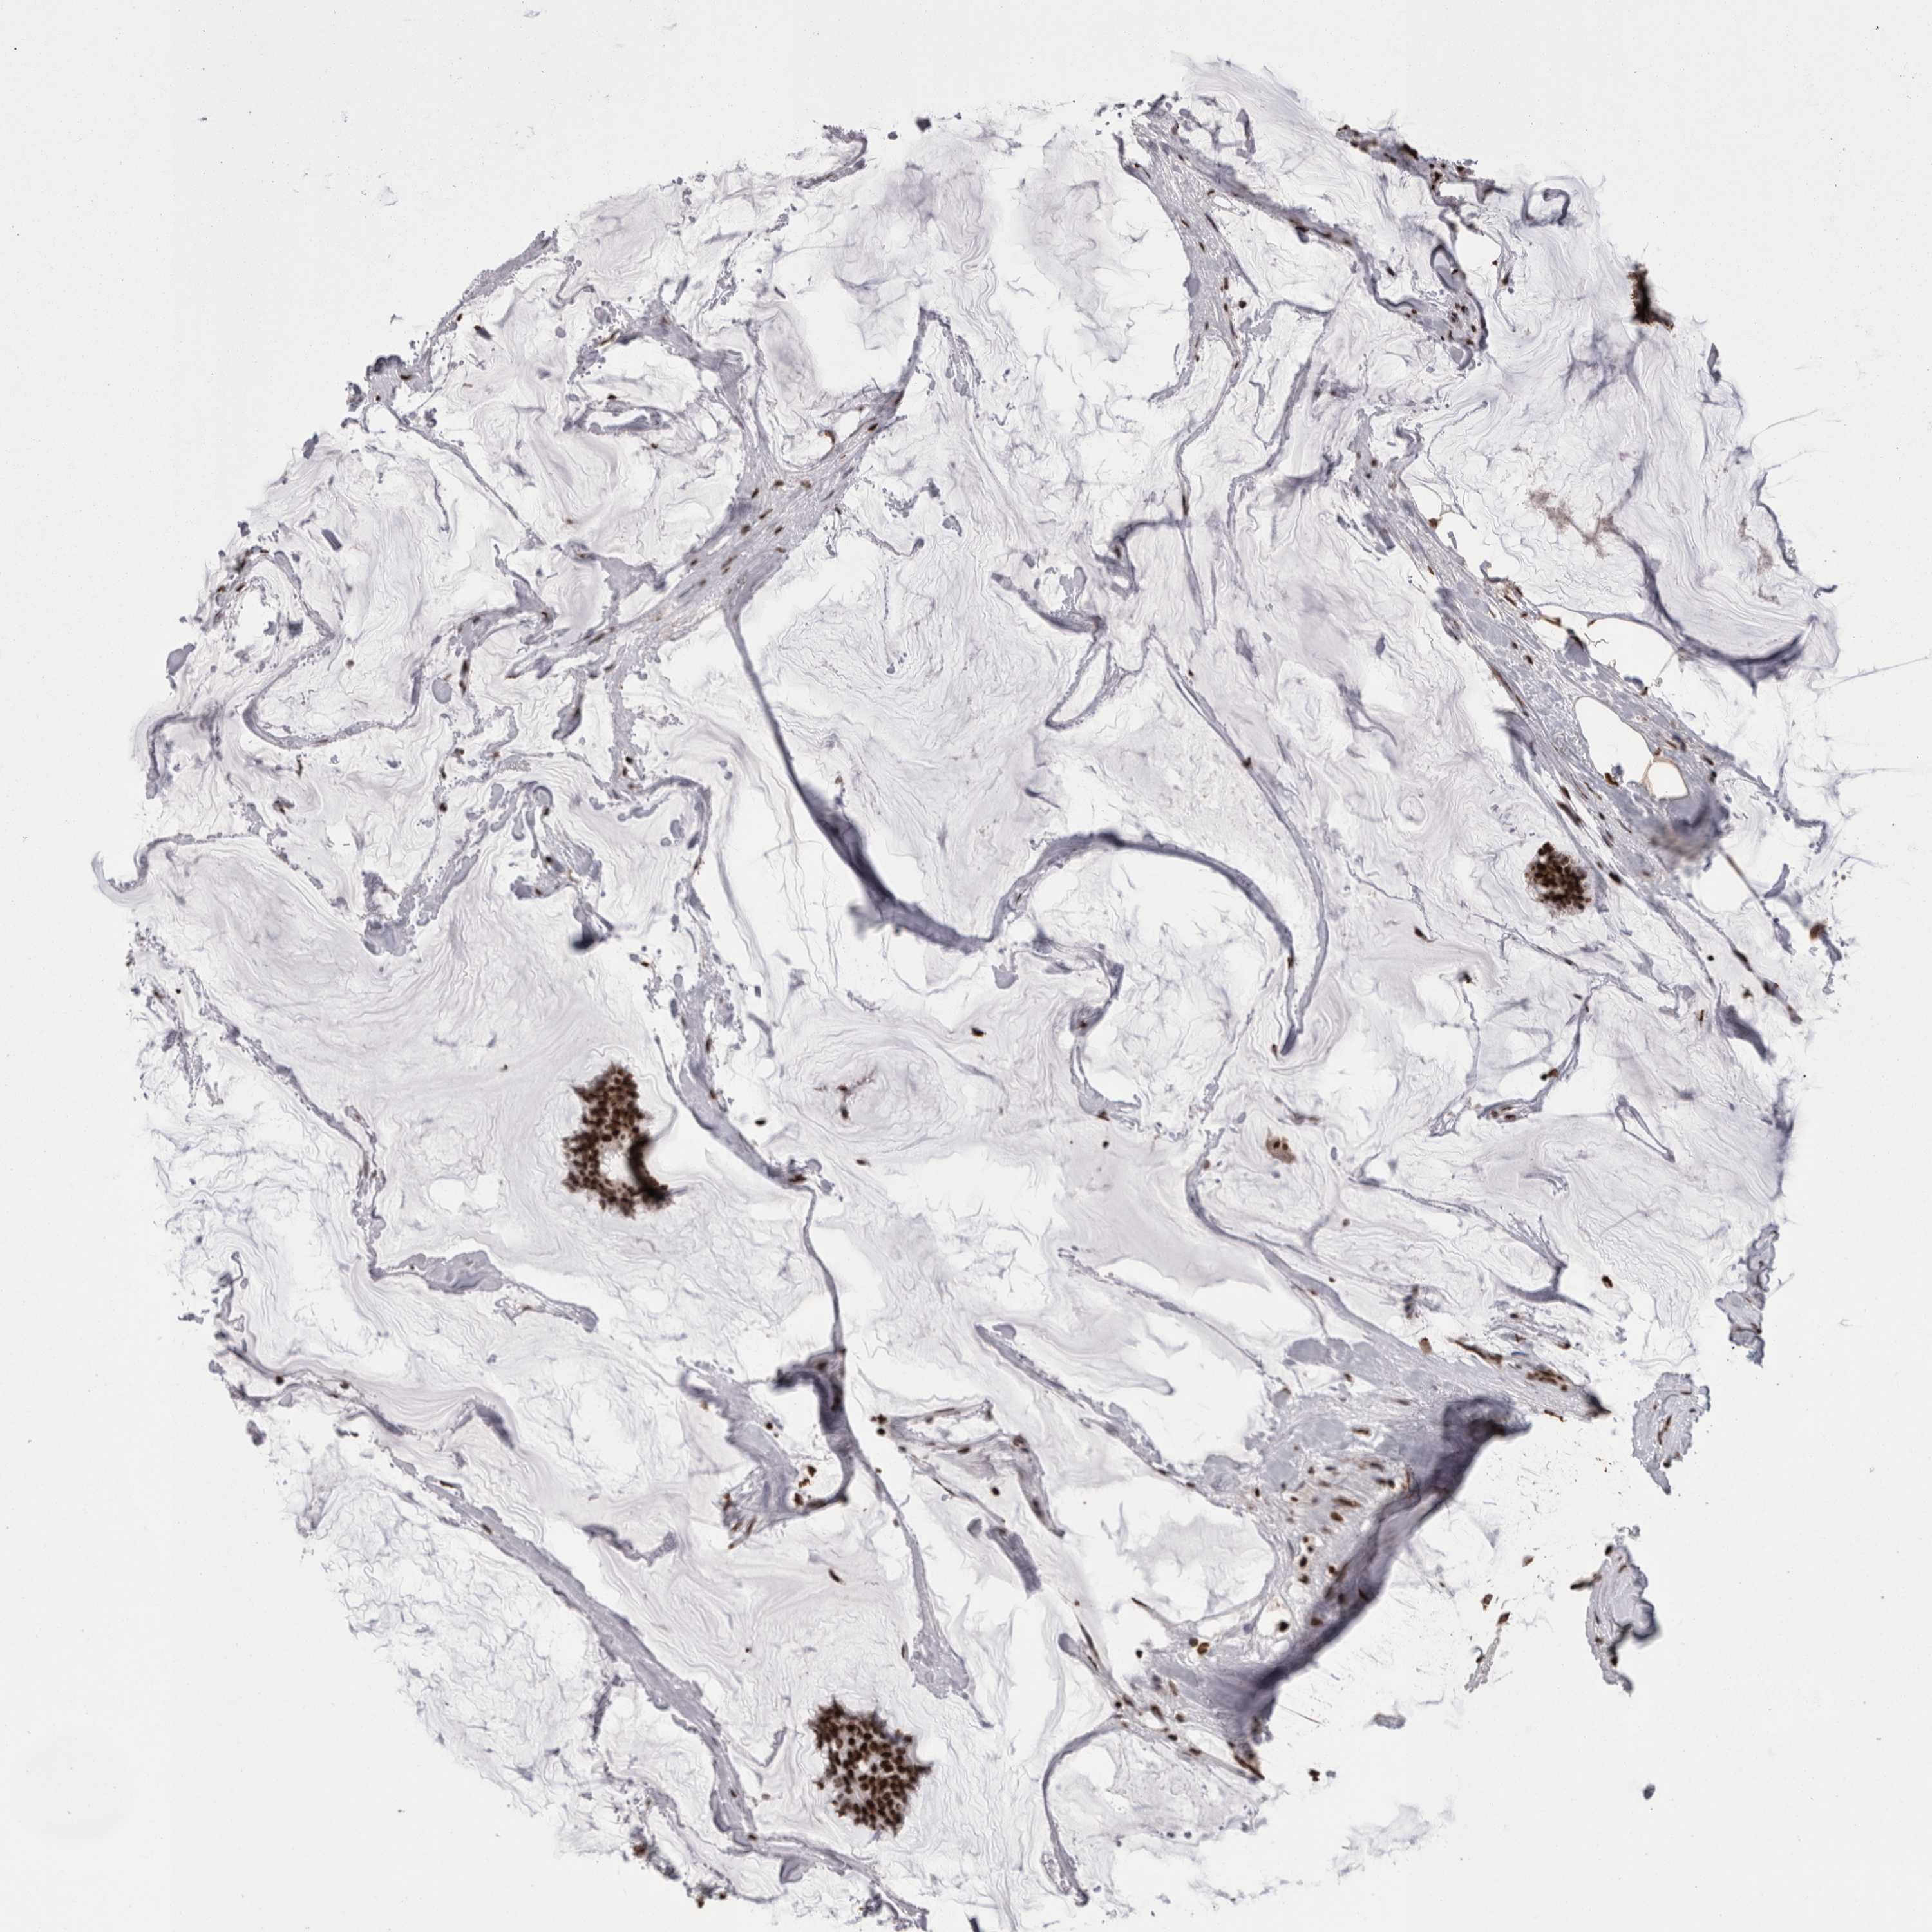

CANCER BREAST CANCER Show tissue menu

BRCA TCGA BRCA VALIDATION PROTEIN EXPRESSION

Breast cancer

Human cancer

Breast invasive carcinoma